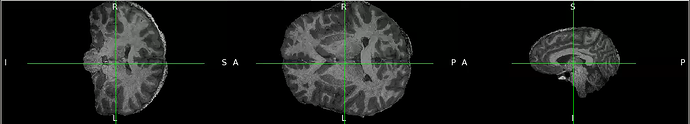

I am trying to extract the brain from T1 weighted image using antsBrainExtraction. However, the result is disappointing because part of the skull can’t be removed. I used MNI T1 weighted image 1mm as template for skull stripping and its brain mask as brain probability mask.

Do you have any kind of suggestion to improve the result ? I attach the image example.